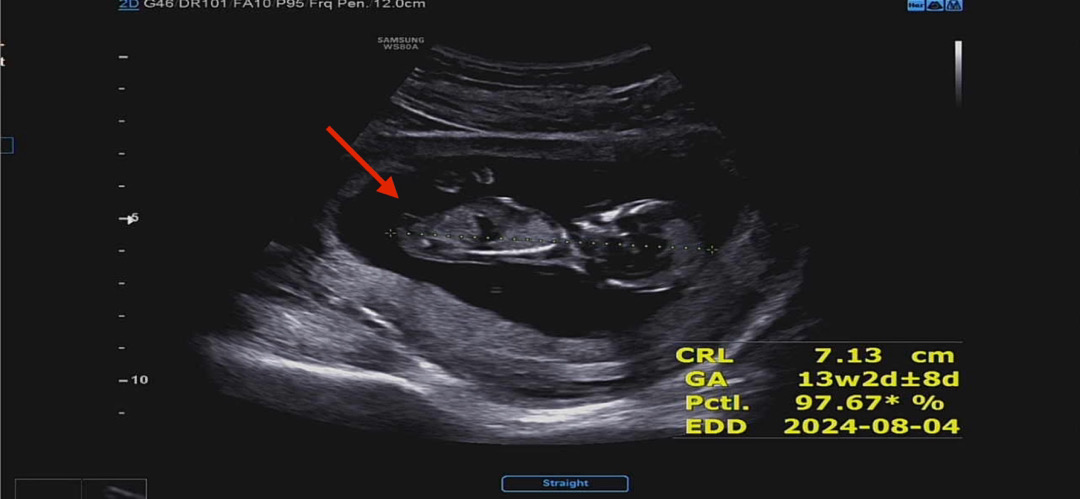

각도법으로 아들??딸??

아직 잘 모르겠는데 뭐가 툭 튀어 나와있는데 아들일까요??

딸 같습니다